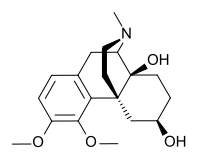

Others

- Drotebanol

- Nalbuphine

Structures

| Other Morphinans | ||||

|---|---|---|---|---|

1-Nitroaknadinine 1-Nitroaknadinine |

14-episinomenine 14-episinomenine |

5,6-Dihydronorsalutaridine 5,6-Dihydronorsalutaridine |

6-Keto Nalbuphine 6-Keto Nalbuphine |

Aknadinine Aknadinine |

Butorphanol Butorphanol |

Cephakicine Cephakicine |

Cephasamine Cephasamine |

Cyprodime Cyprodime |

Drotebanol Drotebanol |

Fenfangjine G Fenfangjine G |

Nalbuphine Nalbuphine |

Sinococuline Sinococuline |

Sinomenine Sinomenine |

Tannagine Tannagine |